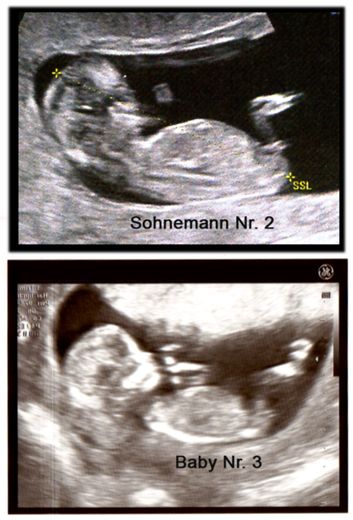

Hello Everyone! Its me again :-) A Gender swaying friend (wanting a Girl) made the The Baby Gender Predictor Test: Am I having a boy or girl? DNA - Test And it said -> BOY! Her second son is 19 Months old and she was pretty careful making the test... Now she went to her doctor’s appointment and the doctor was sure it’s a Girl!! What do you think? Picture 1 : (NT-Scan – Baby Nr.3 -> Is the current pregnancy ) Sohnemann 2 is her second Boy ;-) Picture 2: 17 weeks pregnant potty scan the arrow should show the girl parts .... So Ladys what do you think any chance itīs a GIRL??? Greetings & Thanks ....

Attachment 10345

Attachment 10346